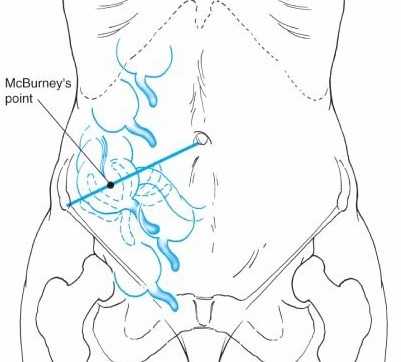

Vị trí của ruột thừa trong ổ bụng rất thay đổi cả trong mối liên hệ với manh tràng lẫn vị trí rất thay đổi của manh tràng trong ổ bụng khiến cho chẩn đoán viêm ruột thừa cấp trong các trường hợp này rất dễ nhầm lẫn với rất nhiều bệnh lý khác [3].

vị trí ruột thừa trong ổ bụng

Hình 4. Vị trí của ruột thừa trong ổ bụng

* Nguồn: theo Nguồn Schwartz(2007) [4]